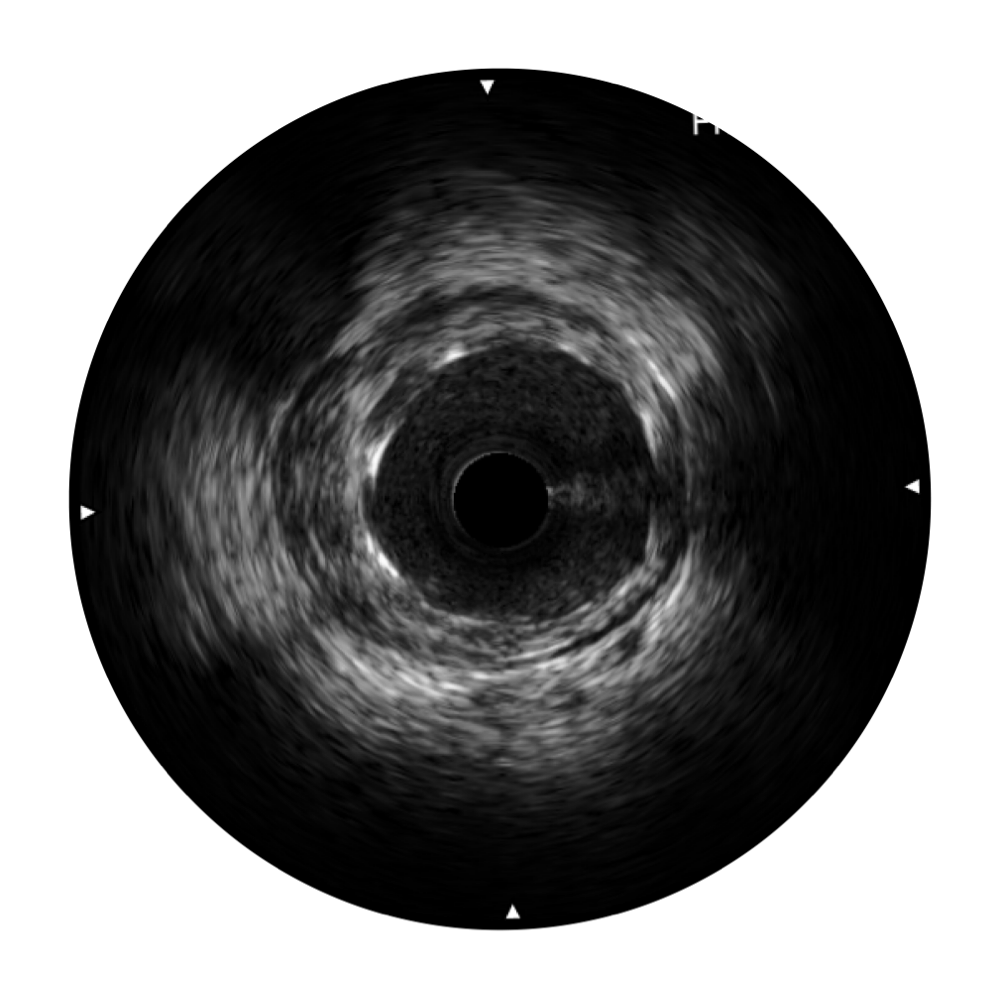

环球UG官网宽频IVUS图像

对比传统IVUS导管成像,环球UG官网宽频IVUS图像的近场支架梁显影更细腻,远场中膜外血管仍清晰可辨,兼顾远中近,兼顾分辨力与穿透深度